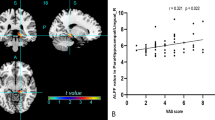

The extrastriatal analysis showed a significant positive correlation between [123I]-FP-CIT binding and subjective heat pain threshold for the left posterior cingulate cortex (p < 0.001) and significant negative correlations for the right secondary visual cortex (p < 0.001) and left insula (p < 0.001) (Fig. 2; Table 3). Using the pain matrix mask, significant correlations were only found in the left posterior cingulate cortex and the left insula.

Concerning the extrastriatal uptake analysis, we found a significant positive correlation between subjective heat pain threshold and [123I]-FP-CIT uptake in the left posterior cingulate cortex (BA31). Thus, lower subjective pain thresholds were associated with lower [123I]-FP-CIT uptake in the posterior cingulate cortex. This area is involved in pain perception processing (Becerra et al. 1999; Bromm 2001; Nielsen et al. 2005), including the “emotional-aversive” component of pain in particular (Bromm 2001). We also found a significant negative correlation in the left posterior insula and in right secondary visual cortex (located outside the volume of interest chosen for the assessment of non-specific activity) but this last region disappeared when applying the pain matrix mask. Thus, lower subjective pain thresholds were associated with higher levels of [123I]-FP-CIT uptake in these regions in PD patients. The insula has been shown to receive a high density of dopamine fibers arising from mesencephalic areas, and dopamine has been implicated in the modulation of pain in the insular cortex (Coffeen et al. 2010; Xie et al. 2009). The insula is involved in the lateral discriminative pain pathways associated with sensory discriminative aspects of pain, and the posterior insula is even considered to be the “third somatosensory region” (S3), because of its relationships with the thalamus, limbic, and multisensory region (contribution to thermosensory, nociceptive, and C-fiber tactile input) (Coghill et al. 1999; Garcia-Larrea 2012; Peyron et al. 2000). Thus, PD patients with lower subjective heat pain thresholds displayed lower levels of [123I]-FP-CIT uptake in the left posterior cingulate cortex, which is part of the medial pain system, and higher levels of uptake in the left insula, which is part of the lateral pain system. These findings suggest a possible imbalance between the medial and lateral pain pathways in PD patients and a predominance of dopaminergic denervation in the medial affective nociceptive pathway related to central neuropathic pain. These findings are consistent with our previous results (Brefel-Courbon et al. 2013) showing that PD patients with central pain display the preferential recruitment of medial pain systems. Moreover, other studies have suggested that chronic neuropathic pain may result from changes in areas associated with the affective/emotional dimension of pain (Hsieh et al. 1995; Moisset and Bouhassira 2007). We suggest the possible involvement of this imbalance between pain pathways in the occurrence of central pain in PD. However [123I]-FP-CIT binds non-selectively to both dopaminergic and serotonin transporters. While [123I]-FP-CIT binding in the striatum mainly reflects presynaptic dopamine transporter availability, binding in the extrastriatal area could reflect serotonin transporter availability. Serotonin transporter is located with high density in the midbrain, thalamus, putamen, and caudate and intermediate binding is found in anterior cingulate and frontal cortex (Schestatsky et al. 2007). According to our results, high regional serotonin transporter binding in the anterior insula was associated with low tonic pain ratings in healthy subjects (Slaoui et al. 2007). Moreover, positive correlations between heat pain ratings and 5HT2A receptors binding in posterior cingulate cortex were also reported (Stern 2014). Hence, we could hypothesize that extrastriatal monoaminergic systems (dopaminergic or serotoninergic) could modulate pain perception in PD patients.